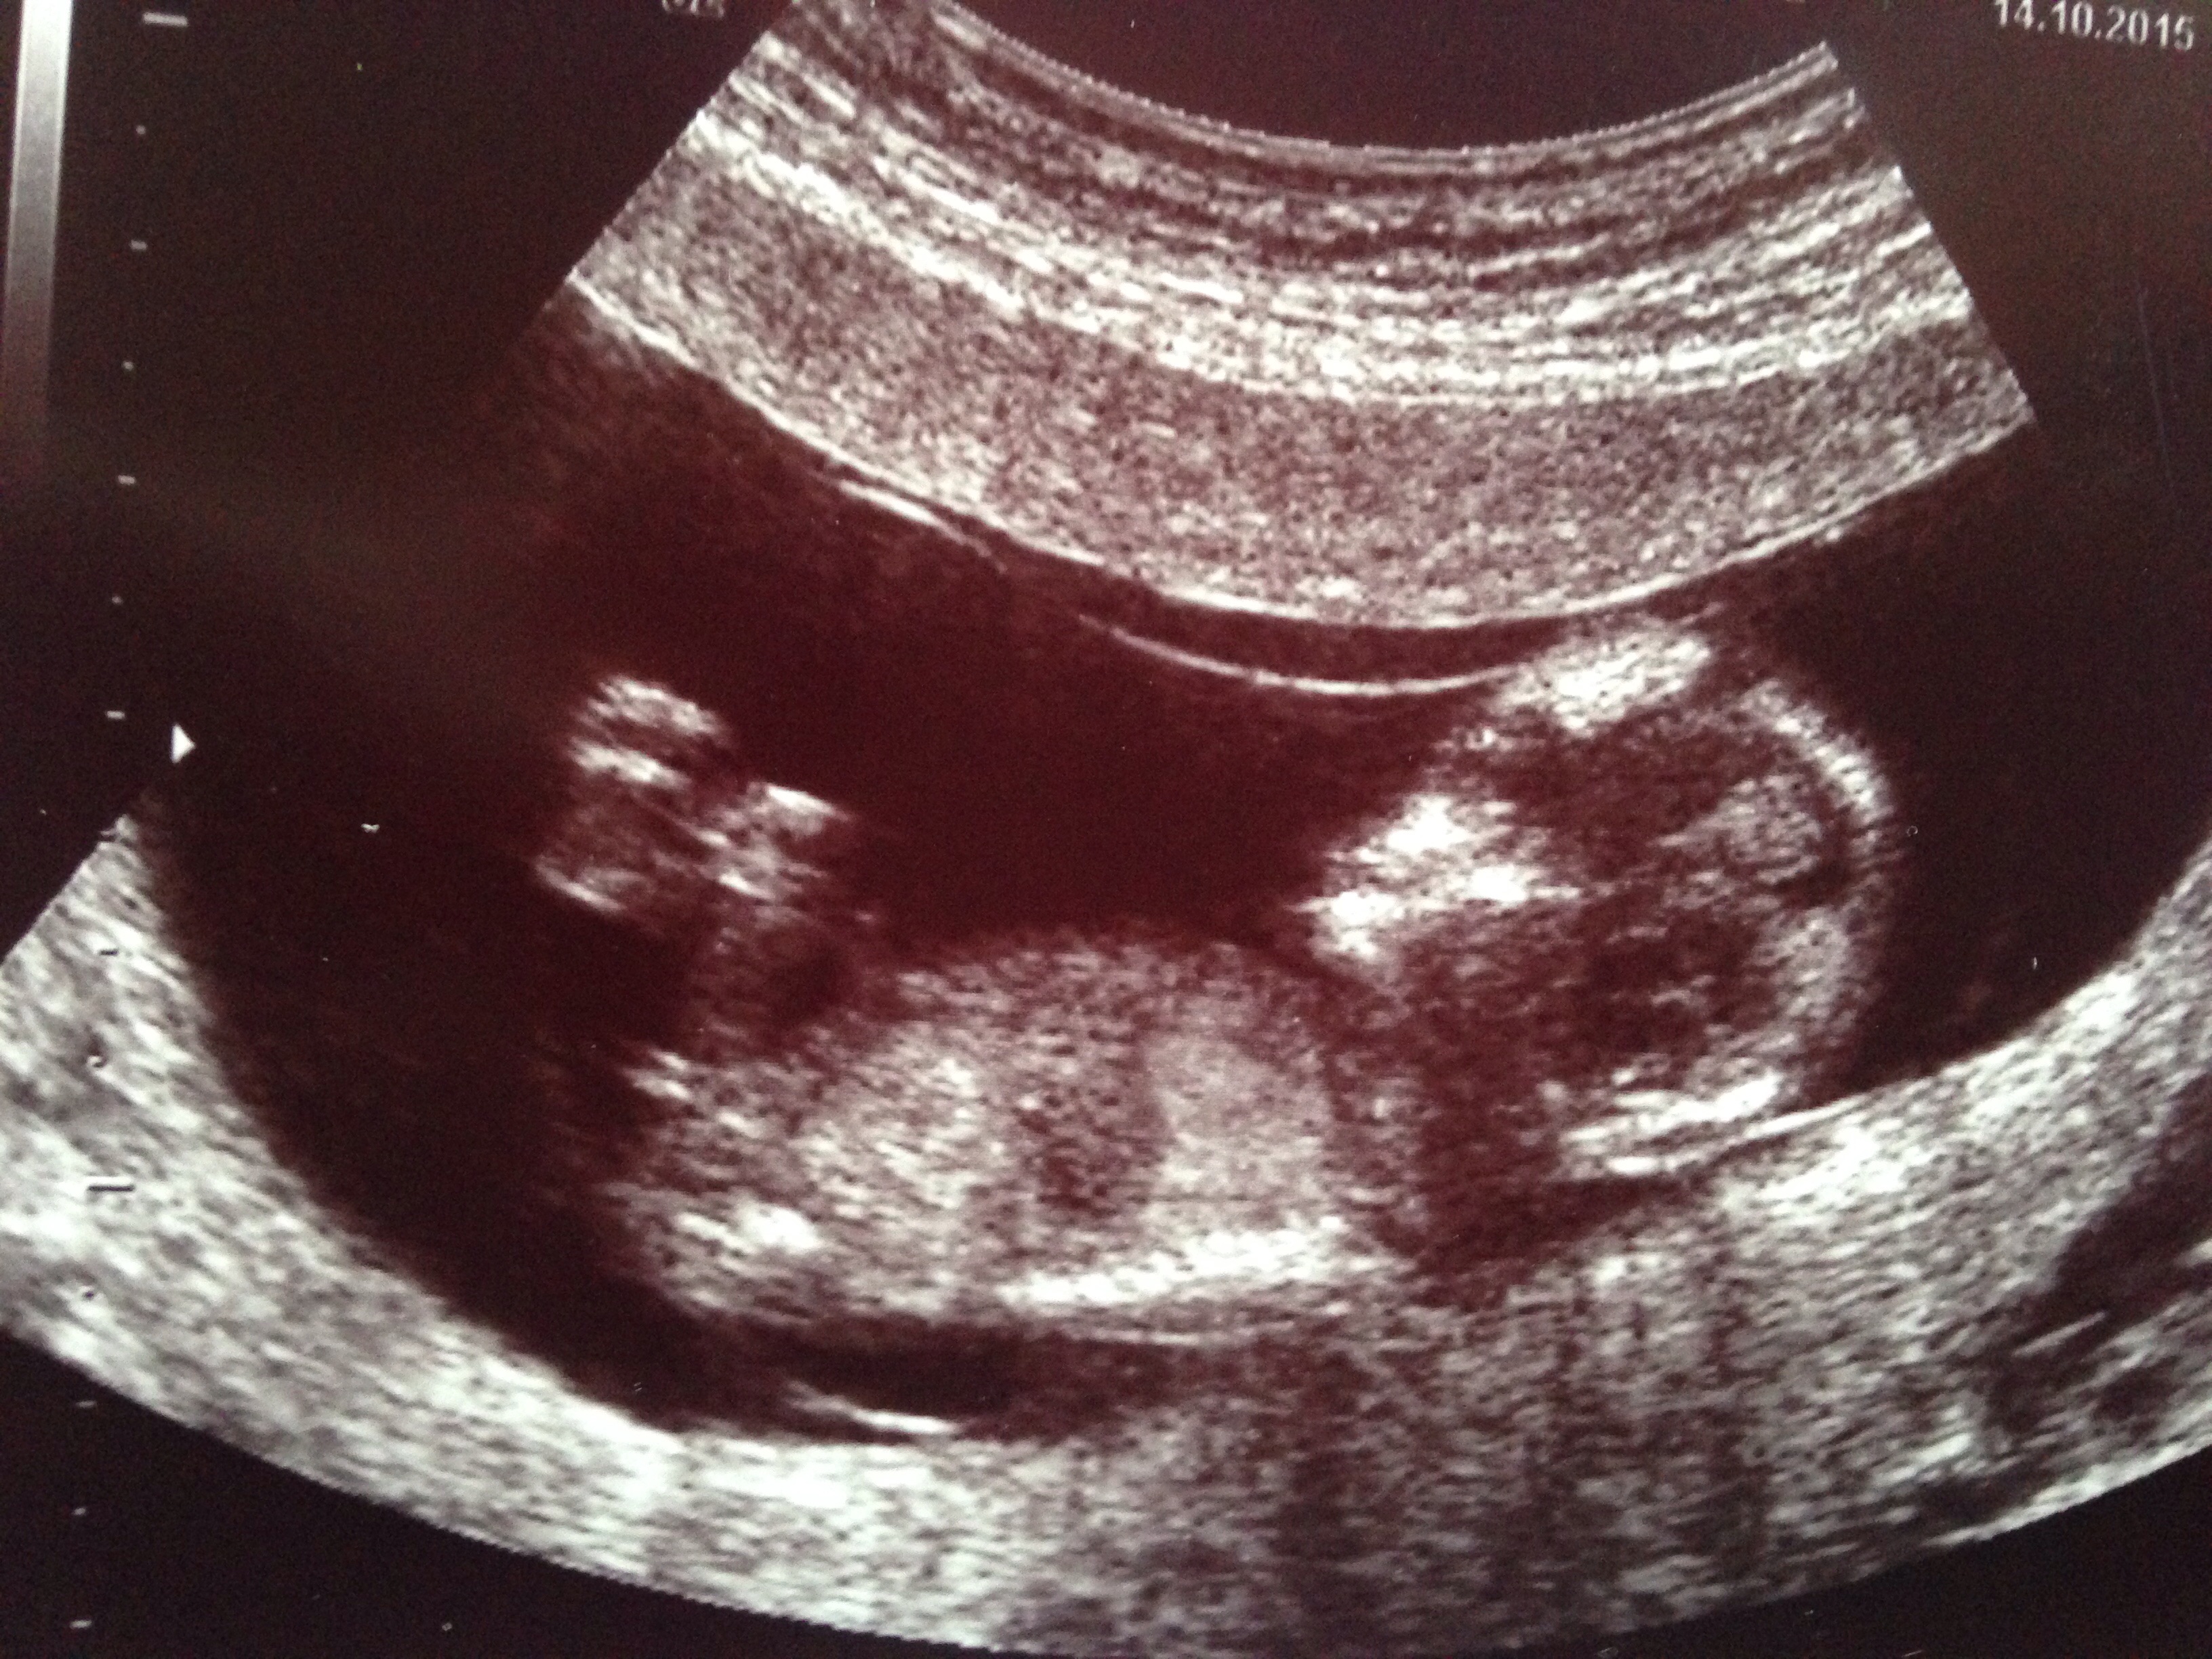

gestation is 13wks - please tell me what you all think?

I'd say boy [emoji4]

looks blue to me

Boy

I would guess boy too; the angle isn't particularly great however the nub is very obvious for 13 weeks. Good luck to her! :) xx

I thought girl from first nub pic. But last nub pic looks more angled up- boyish